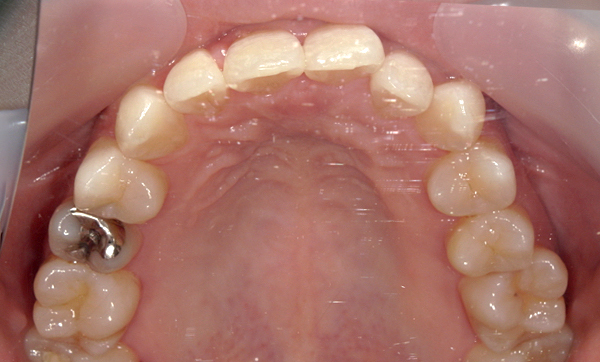

症例_009 「上下の前歯」症例

治療期間:7ヶ月金額:54万円+税20代女性捻転歯一部の反対咬合前歯のガタガタ